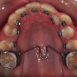

Interdisciplinary Treatment of Patients with Deep Overbite and Parafunctional Activity

Bruxism is defined as parafunctional grinding of teeth and due to the excessive wear of the posterior teeth, patients with long-standing bruxism often have pathological deep overbite. For many decades, treatment of bruxism and deep overbite was focused on reshaping the bite for achieving an occlusion free of deviations. Despite large efforts, the management of bruxism and subsequent deepening overbite was not obtained.